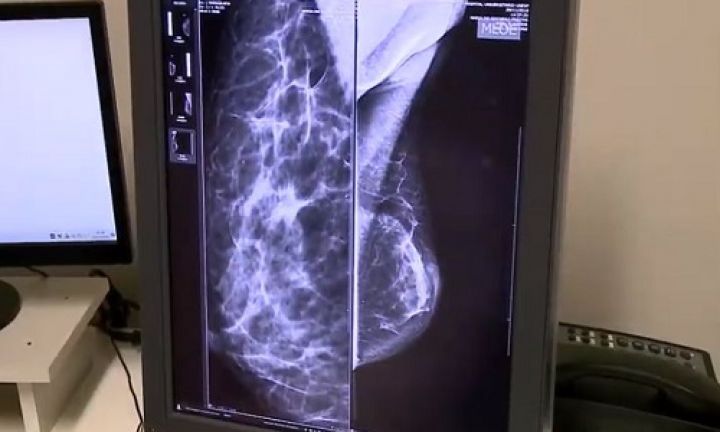

legenda: Espaço de unidade ligada à Unesp conta com equipe multidisciplinar para oferecer tratamento a pacientes com câncer de mama

Fonte da Foto: Governo de SPNo Hospital das Clínicas de Botucatu, vinculado à Universidade Estadual Paulista (Unesp), o Centro de Avaliação em Mastologia conta com uma equipe multidisciplinar que atua para diminuir o tempo de espera por exames na rede pública de saúde e oferece um tratamento completo às pacientes da região que buscam o serviço.

Fundado no início da década de 1990, o espaço é referência na região de Botucatu em relação à saúde mamária. Um dos diferenciais do local é a estrutura completa para o atendimento (desde o diagnóstico até o tratamento) e a realização de exames de imagem.